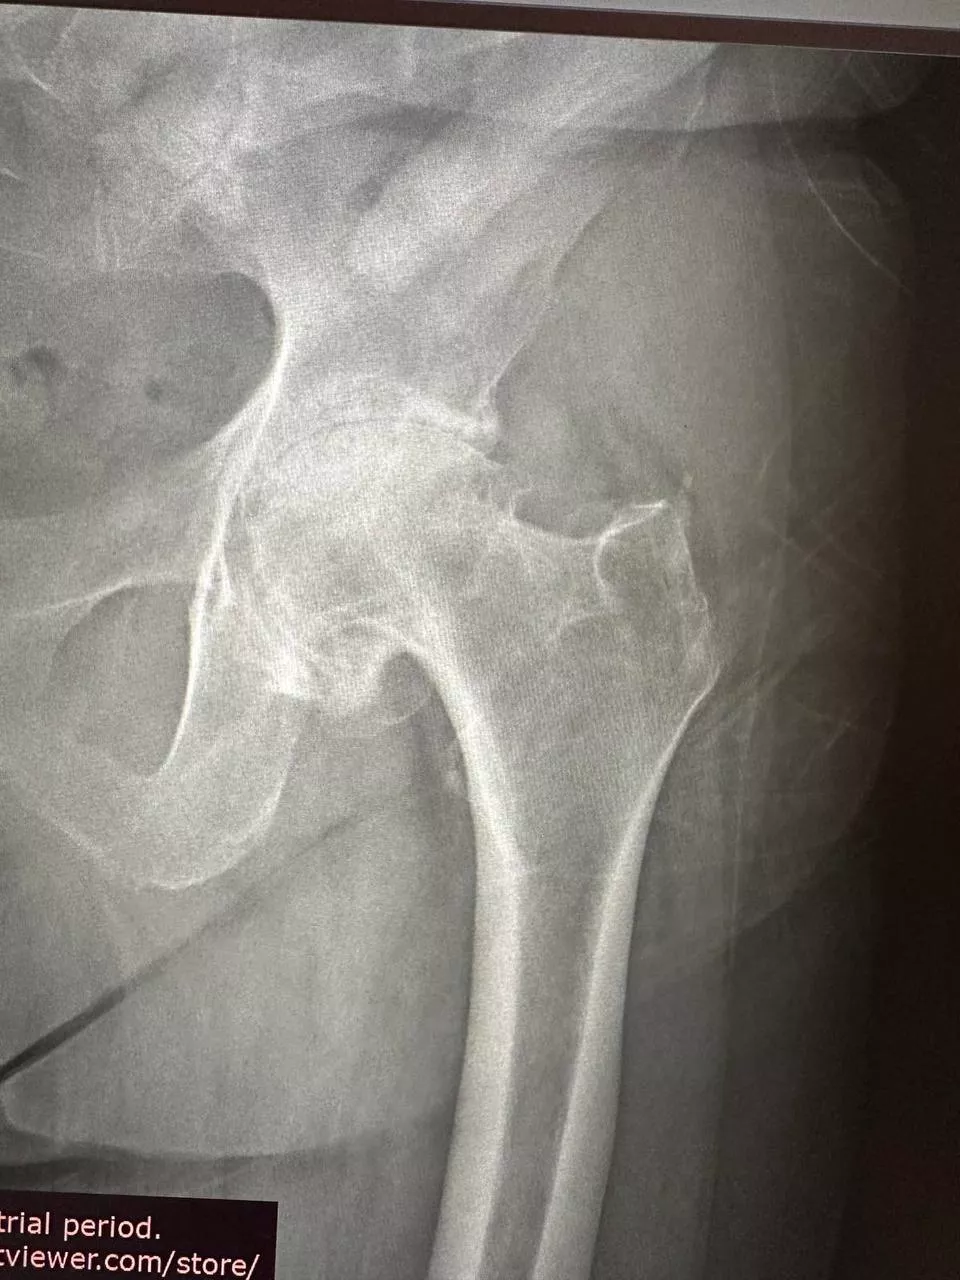

Ендопротезування кульшового суглоба

Заміна кульшового суглоба — одна з найефективніших операцій, яка вважається "золотим стандартом" в ортопедії. Цей вид хірургічного втручання виконується для лікування важких захворювань суглобів і відновлення їхньої рухливості. Під час операції пошкоджений суглоб замінюється на штучний імплантат, що дає змогу значно зменшити біль і повернути свободу рухів. Ендопротезування допомагає відновити повноцінне функціонування кульшового суглоба, забезпечуючи пацієнту активне і комфортне життя.

- Рентгенографія суглоба — дає змогу побачити структуру і стан кістки, оцінити ступінь пошкодження і виявити можливі деформації.